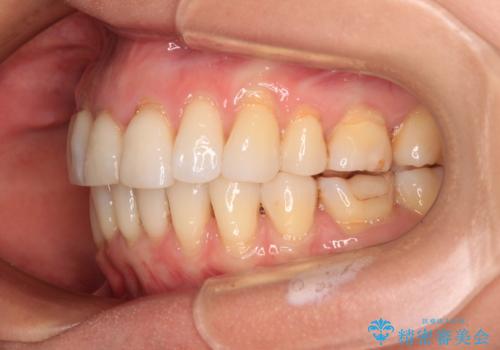

- 上の前歯の出っ歯を治したいとのことで来院された患者様です。

後戻りによる再矯正というもともあり、インビザラインを希望されていました。

上顎の歯は後方移動とIPR(歯と歯の間を削る)によって口元が引っ込むように、下顎は歯列全体の拡大とIPRによって上顎とバランスよく咬み合うように設計し、インビザラインにより治療を行うこととしました。

治療を開始して暫くして、勤務先から2年以上帰国することができず、それまでの移動がほとんど後戻りしてしまい、帰国後に再度後戻りをリカバリーするための治療を行うこととなりました。

5年以上の治療期間がかかりましたが、気になっている部分を改善することができました。